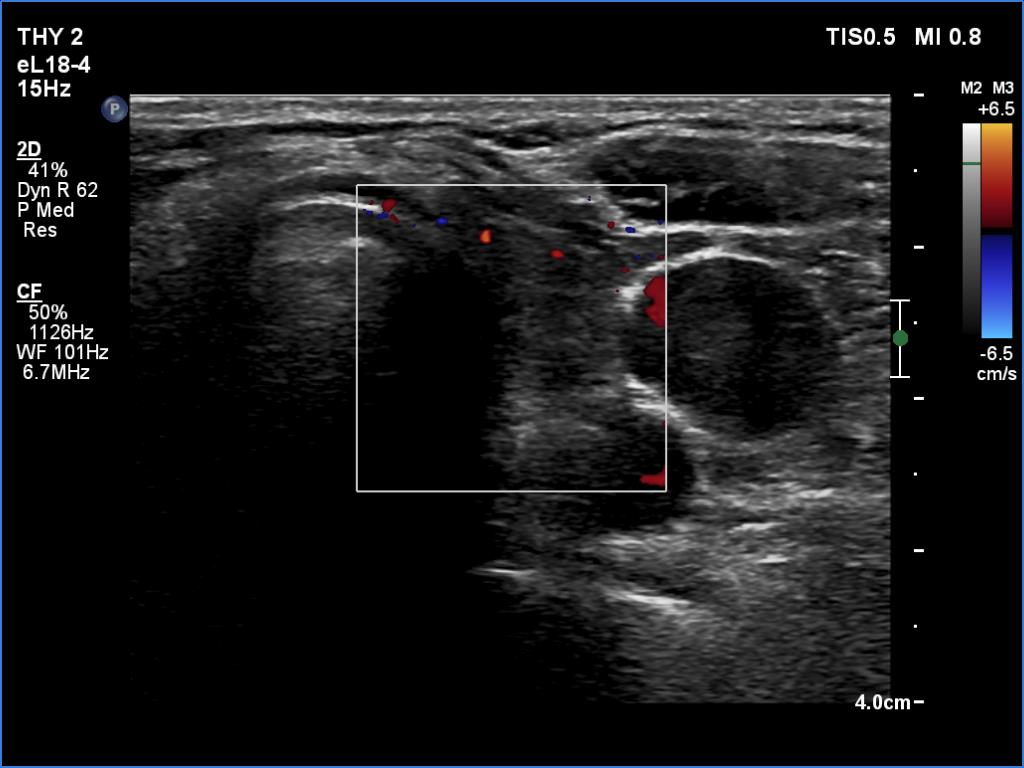

The operated thyroid - case 1700 (ultrasonographic picture 6)

Left lobe, transverse scan, color Doppler mode. The vascularization is scanty.